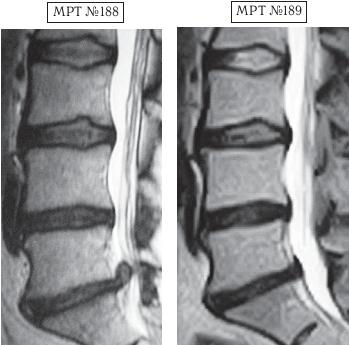

На МРТ № 190 наблюдается состояние поясничного отдела позвоночника после хирургического вмешательства в сегменте LV-SI, протрузии межпозвонковых дисков в сегментах LIII—LIV и LV-SI, грыжа межпозвонкового диска, осложнённая секвестром с краниальной миграцией в сегменте LIV—LV, стеноз спинномозгового канала.

На МРТ № 191 наблюдается состояние поясничного отдела позвоночника после лечения методом вертеброревитологии: отсутствие секвестрированной грыжи межпозвонкового диска, отсутствие стеноза спинномозгового канала.

Должен отметить, что это был на редкость дисциплинированный пациент, он строго выполнял все предписания и назначения. И, конечно же, результат не заставил себя ждать — между МРТ № 190 и МРТ № 191 разница всего три месяца! А буквально через полтора года он взошёл на пьедестал почёта. Это была настоящая его победа, в первую очередь над обстоятельствами, своими болезнями, недоверием окружающих и главное — над самим собой!